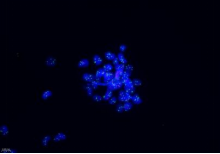

分子病理染色 | FISH |

|